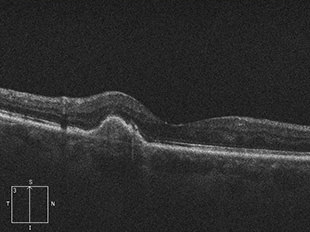

病的近視における脈絡膜新生血管

病的近視とは、近視のなかでも眼軸長(眼の前後の長さ)が伸びているため、さまざまな眼底の病気を伴うものをさします。

病的近視における脈絡膜新生血管は、病的近視の方の5~10%に起こる病気で、新生血管からの出血や、もれ出た血液成分(滲出液)があるため、見えない部分ができたり、ゆがみが生じたりします。

治療前

治療後

治療前 OCT

治療後 OCT